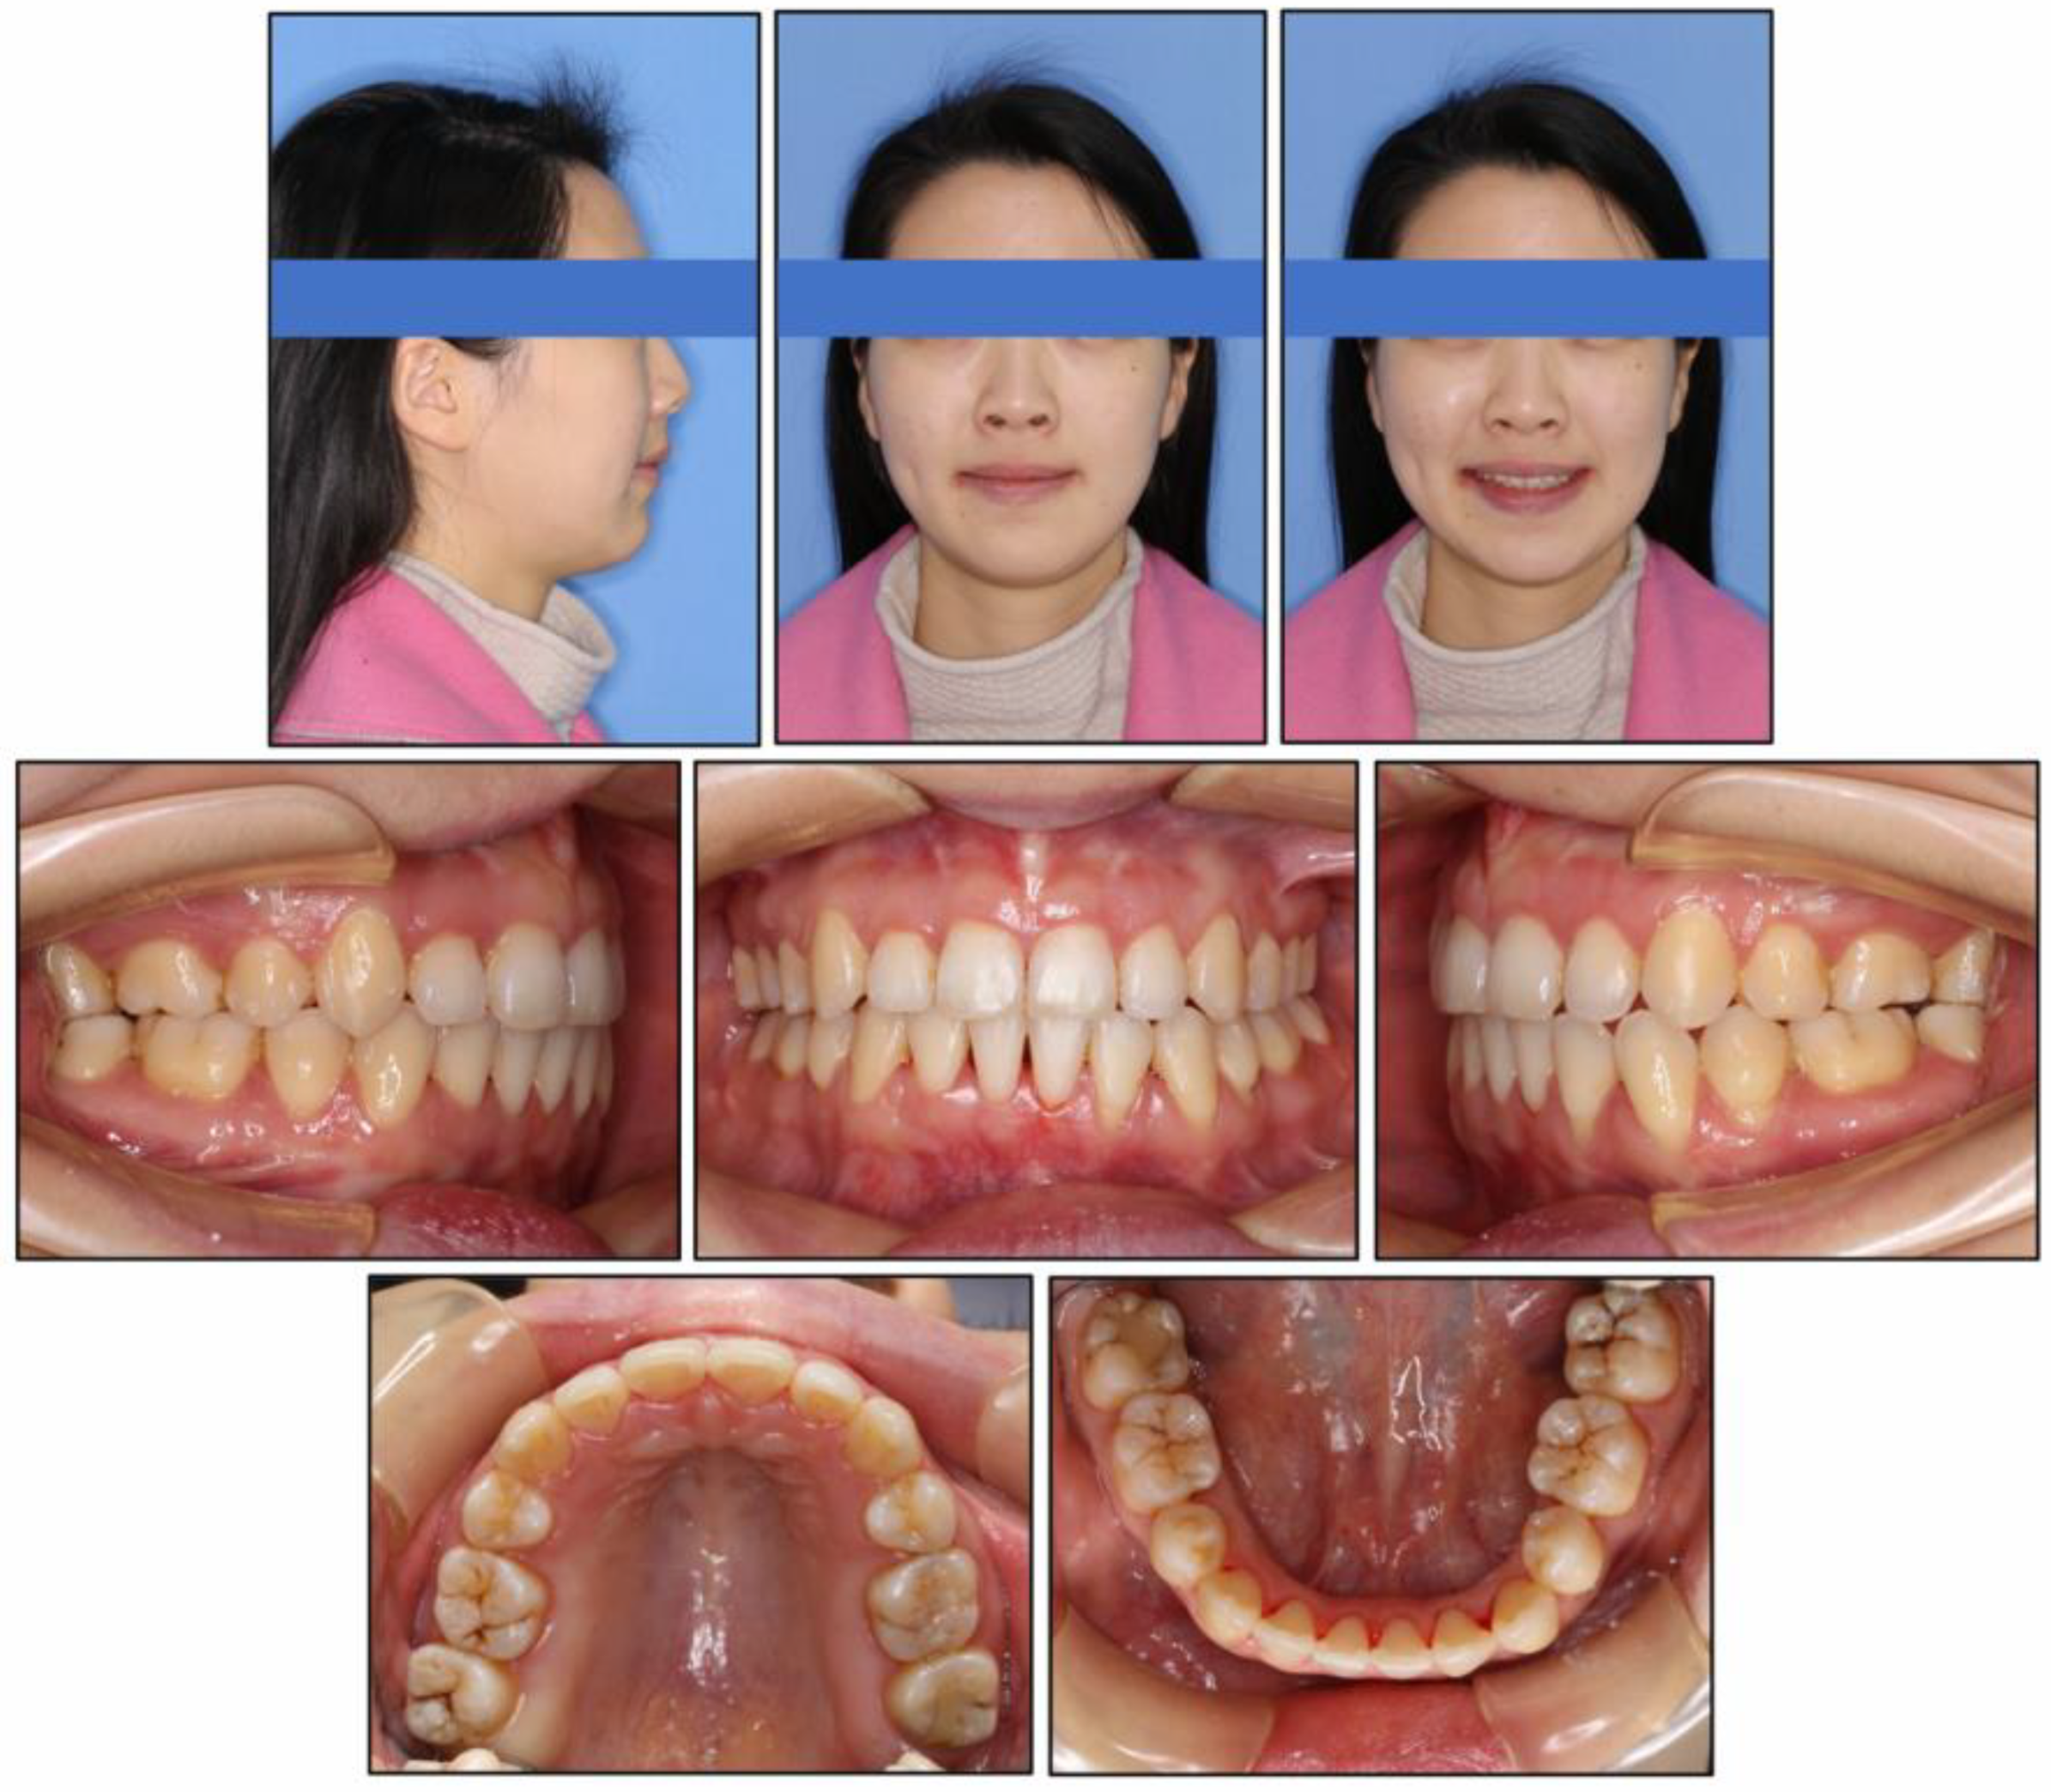

2.1. Diagnosis and Etiology